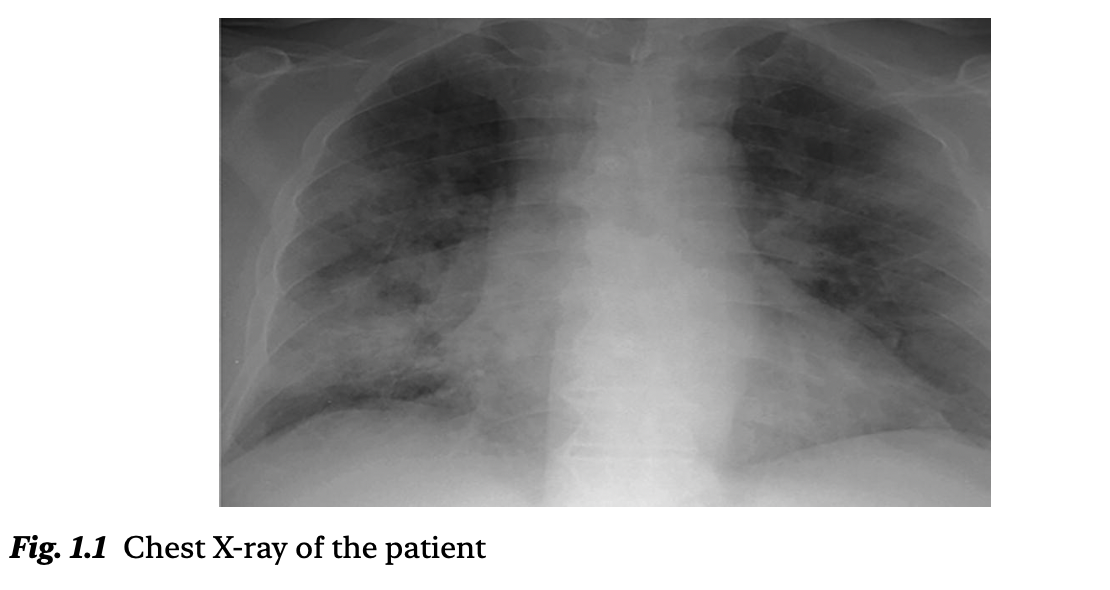

一名58岁的肥胖男性,BMI为34,患有糖尿病和高血压,被诊断为急性胰腺炎。由于精神状态改变和呼吸困难持续4小时,他从病房转入ICU。入ICU时,他的格拉斯哥昏迷评分(GCS)为13/15,表现为嗜睡但可被唤醒,呼吸频率为34次/分,在使用重复呼吸面罩以12升/分钟吸氧的情况下,血氧饱和度(SpO₂)为89%。心率为120次/分,血压记录为110/70 mmHg。其胸部X线片见图1.1。

临床印象:由急性重症胰腺炎引起的肺外急性呼吸窘迫综合征(ARDS)。由于持续的器官功能障碍、呼吸功能恶化及精神状态改变,决定进行气道保护和机械通气。计划实施气管插管。

心脏和肺部超声有助于快速、准确地进行床旁评估。进一步的脉搏血氧测定、动脉血气分析,以及胸部X线或CT等影像学检查(如有条件)可帮助评估气道管理和插管的紧迫性。但这些检查不能替代临床判断,也不应延误气管插管。

拍摄胸片以确认气管导管位置、双肺扩张情况及口/鼻胃管位置。